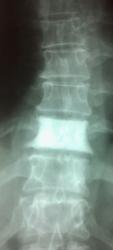

В дифряд - бластную фазу болезни Педжета, хотя "рамы" нет.

21.pedzheta_bolezn.jpg

21.pedzheta_bolezn.jpg197.82 кб